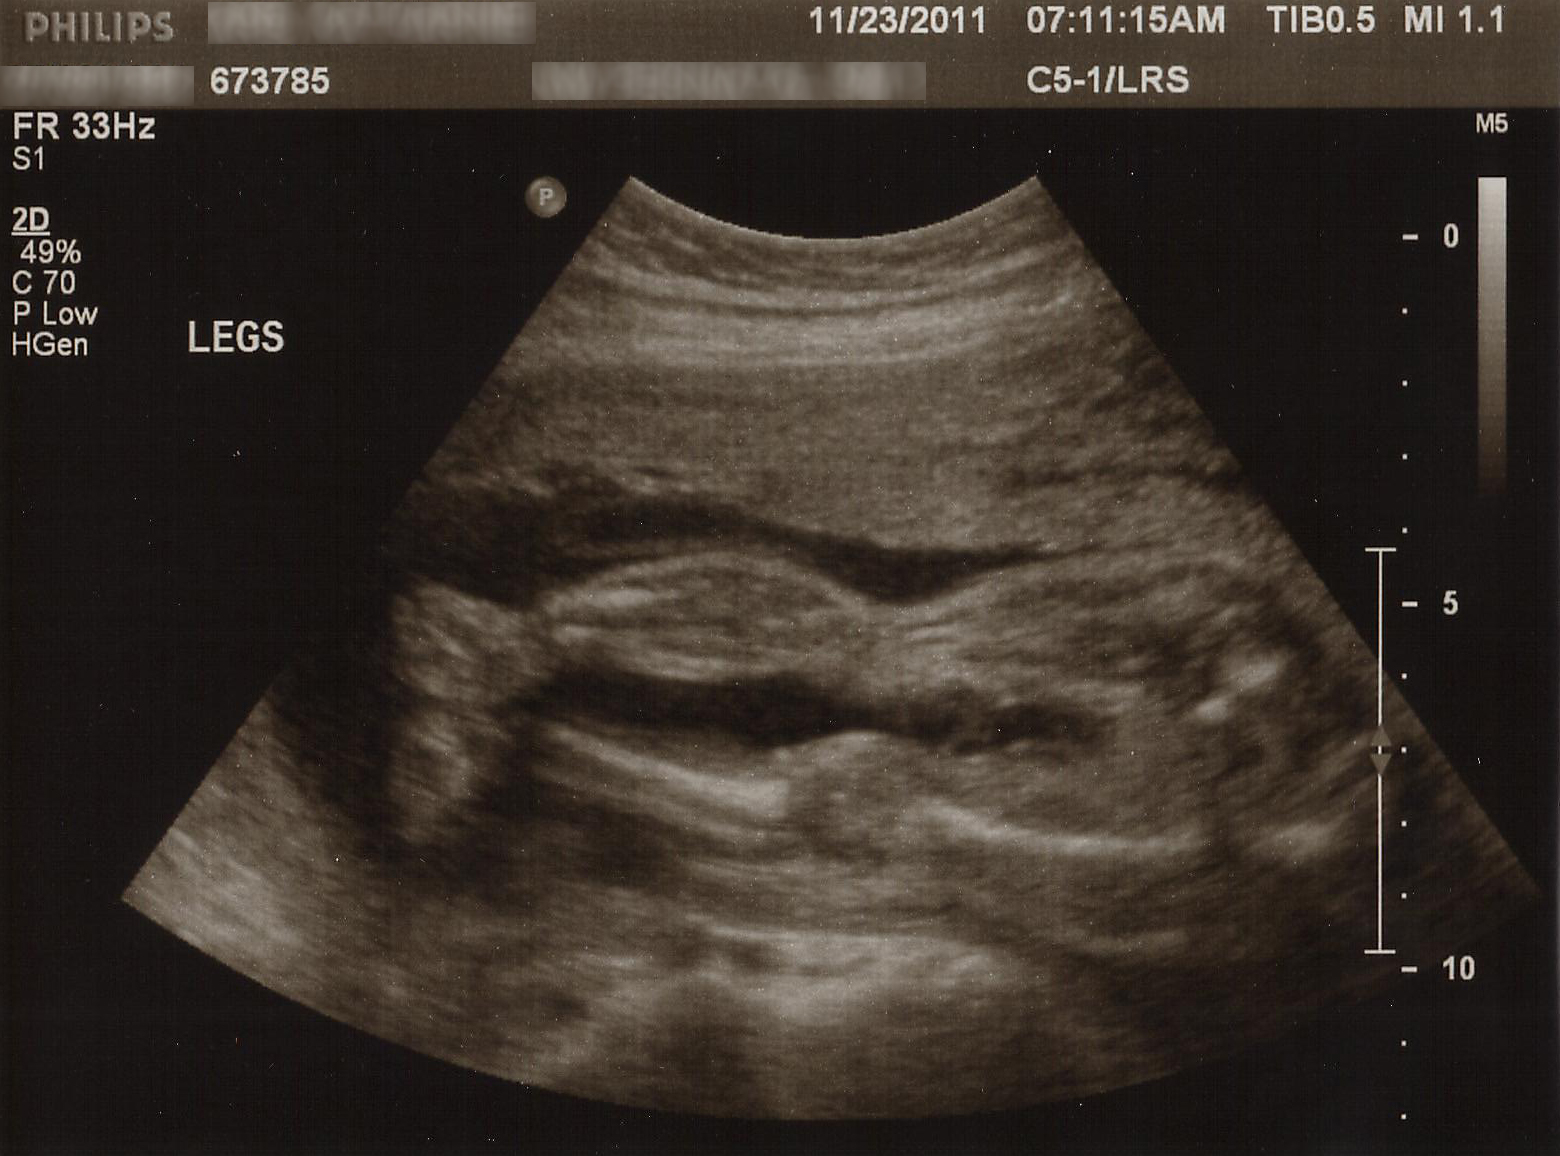

Today we had our follow-up ultrasound. At our 20 week scan, we found out that I had complete placenta previa, and that baby had a CCAM on her lung and possibly also VSD. It was so stressful and upsetting. I’ve been trying very hard not to worry about this ultrasound for the last month.

But today, everything was good news. The CCAM is still tiny. We’ll have to keep checking up on it to make sure it doesn’t suddenly become much larger, but the doctor anticipates that it will actually start shrinking pretty soon and won’t be an issue at all. My placenta appears to be moving out of the way. Instead of complete, it’s now only partial. Fingers crossed that 16 more weeks sees that sucker moving completely out of the way.

The best news was that there was no evidence of the possible VSD. That is a huge weight off my shoulders, since it was the thing I was most worried about.